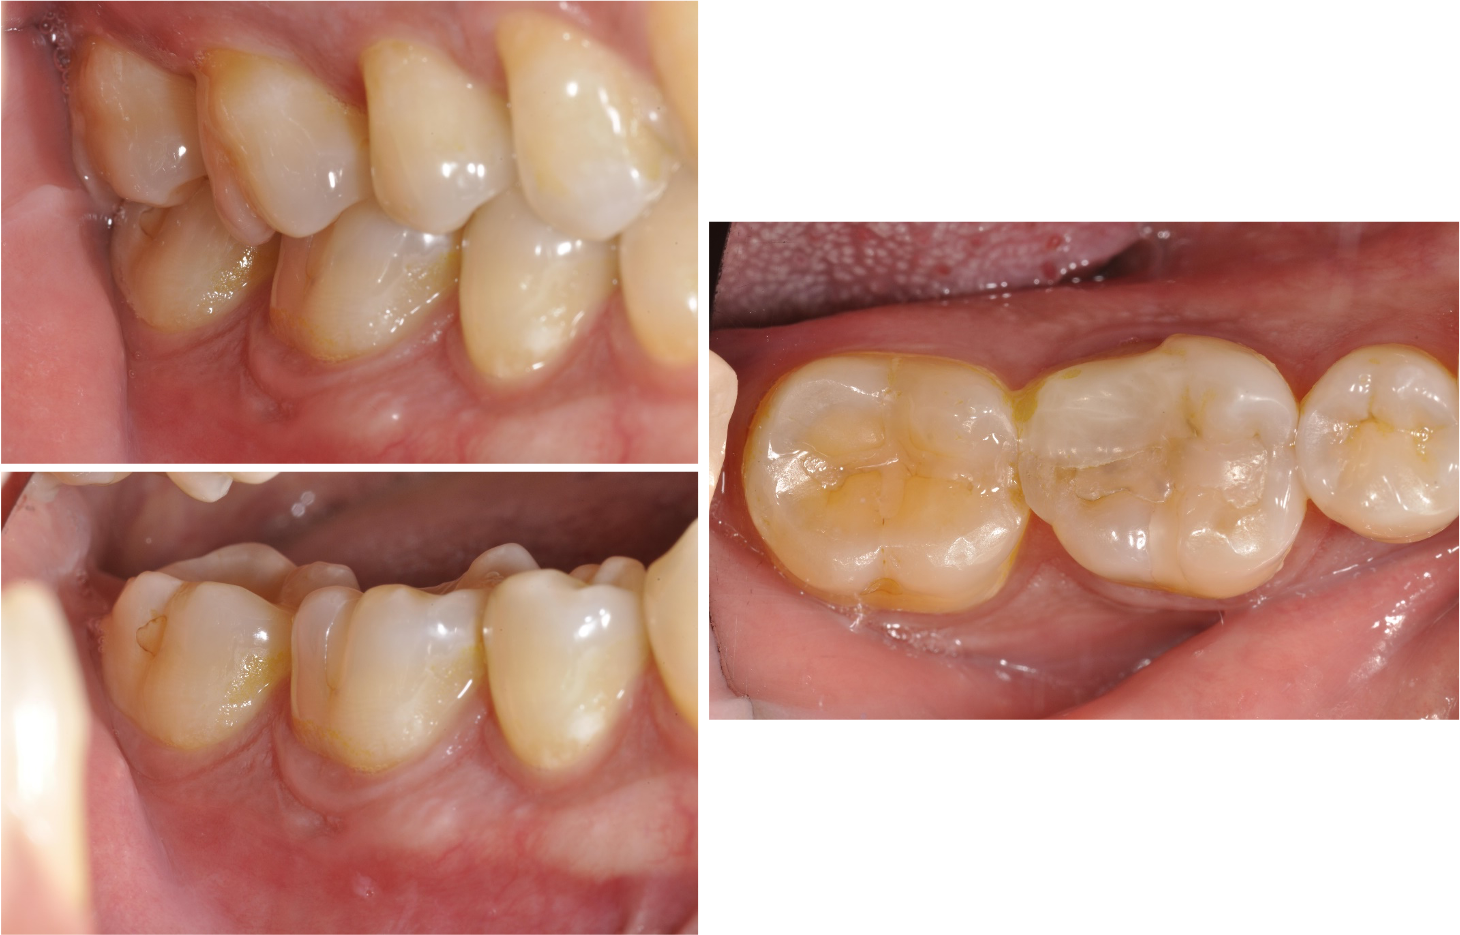

治療前,牙齒破損與蛀牙

治療前,蛀牙與根尖破壞